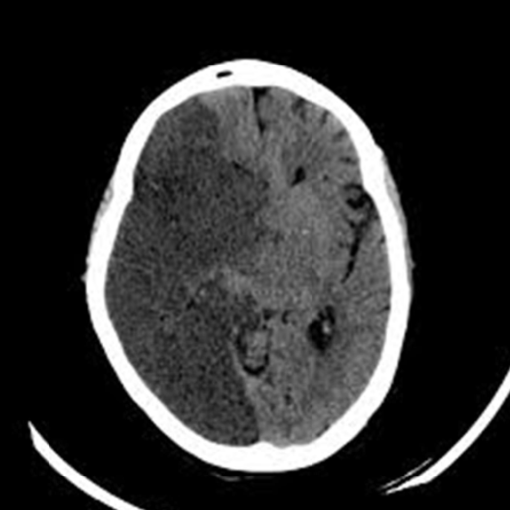

occlusion of this artery leads to coma with pinpoint pupils, flaccid quadriplegia, and sensory loss, and variable CN abnormalities

basilar artery infarct